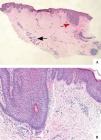

Incision biopsy of the armpit showed hyperkeratosis and irregular acanthosis. The spongiosis involved the epidermis as well as the hair follicle. The dermis had a mild, superficial, perivascular and perifollicular lymphocytic infiltrate as well as some histocytes and eosinophils. We could find some dilated sweat gland ducts in the deep dermis (Figure 2). We diagnosed the patient with FFD based on the typical clinical parameters and histopathological characteristics.

A - Hematoxylin & eosin, X10. Hyperkeratosis and irregular acanthosis, some mononuclear cells (indicated by red arrow) forming an infiltrate around hair follicle; dilation of sweat gland ducts (indicated by black arrow) in the lower-mid dermis. B - Hematoxylin-eosin, X100. Follicular spongiosis, some lymphocytes and a few histocytes and eosinophils